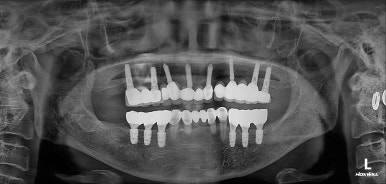

수술 후 촬영한 치과용 파노라마 사진에서, 정~말 깔끔하고 예쁘게 식립된 임플란트를 보실 수 있습니다.

아래턱뼈 내부에는 하치조신경이라는 감각신경이 주행하고 있는데요, 네비게이션 임플란트를 통해 수술 후 감각마비 없이 깔끔하게 마무리 되었습니다.

치과용 파노라마 사진을 보면 뭔가 좌우 대칭으로 깔끔하게 완성된 아래턱 양쪽 어금니 임플란트를 보실 수 있어요!!

치과용 파노라마 엑스레이만 보아도, 임플란트 여섯개가 깔끔하게 제작된 것을 보실 수 있을겁니다.